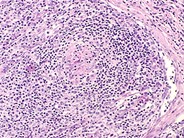

Home » Without Label » What Is Angioimmunoblastic T-Cell Lymphoma - Histopathology images of Angioimmunoblastic T-cell ... : Angioimmunoblastic t cell lymphoma (aitl) is a peripheral t cell lymphoma characterized by systemic disease, a polymorphous infiltrate involving lymph nodes, and a prominent proliferation of high endothelial venules and follicular dendritic cells (who 2008).

Amira m elbendary, mbbch, msc; What types of doctors treat lymphoma? Its characteristic feature is the formation in the lymph nodes of seals with an infiltrate in the form of immunoblasts and what is important, when pressing on the swollen lymph nodes of pain, the patient does not feel that it speaks not of the inflammatory, but of the. Males have a higher incidence than females. These lymphomas start in the skin. Angioimmunoblastic t cell lymphoma (aitl) is a peripheral t cell lymphoma characterized by systemic disease, a polymorphous infiltrate involving lymph nodes, and a prominent proliferation of high endothelial venules and follicular dendritic cells (who 2008). In 1974, frizzera et al 1 described angioimmunoblastic lymphadenopathy with. It affects older individuals, with an average age these include skin rashes, joint pain, and some blood abnormalities. What is the treatment for lymphoma? Other occurrence of the disease in general. Atlas genet cytogenet oncol haematol. (this etymology is missing or incomplete. Dirk m elston, md more.